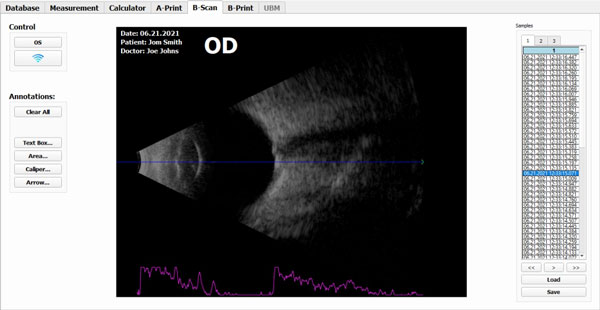

B-Scan

- Exceptional signal to noise ratio yields a deep penetration while maintaining high resolution image.

- 10 MHz transducer and 55 degrees of viewing angle with 256 scan lines produces a high quality sonogram.